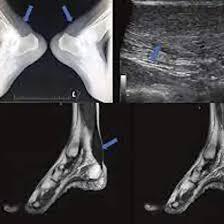

A NCCT (non-contrast computed tomography) of the right ankle joint is a radiology scan that uses X-rays and a computer to create images of the right ankle joint bones and its soft tissues to detect abnormalities in the right ankle joint. It is an effective technique to diagnose issues like injuries in the tendon, fracture to the bones, trauma to the right ankle and infections in the right ankle joint.

A NCCT (non-contrast computed tomography) of the right ankle joint is a radiology scan that uses X-rays and a computer to create images of the right ankle joint bones and its soft tissues to detect abnormalities in the right ankle joint. It is an effective technique to diagnose issues like injuries to the tendons, fractures to the bones, trauma to the right ankle, and infections in the right ankle joint.